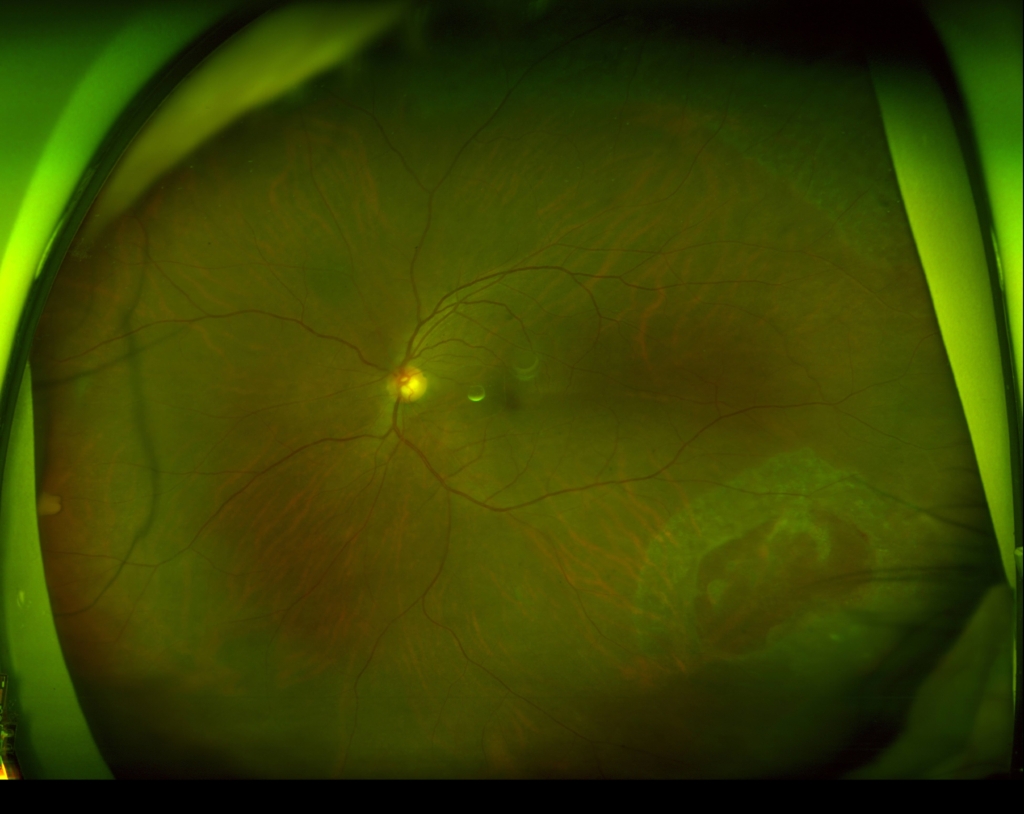

3時から8時に黄斑剥離を伴う胞状網膜剥離があり、4時に弁状裂孔がみられる。

12時から2時に格子状変性がみられる。